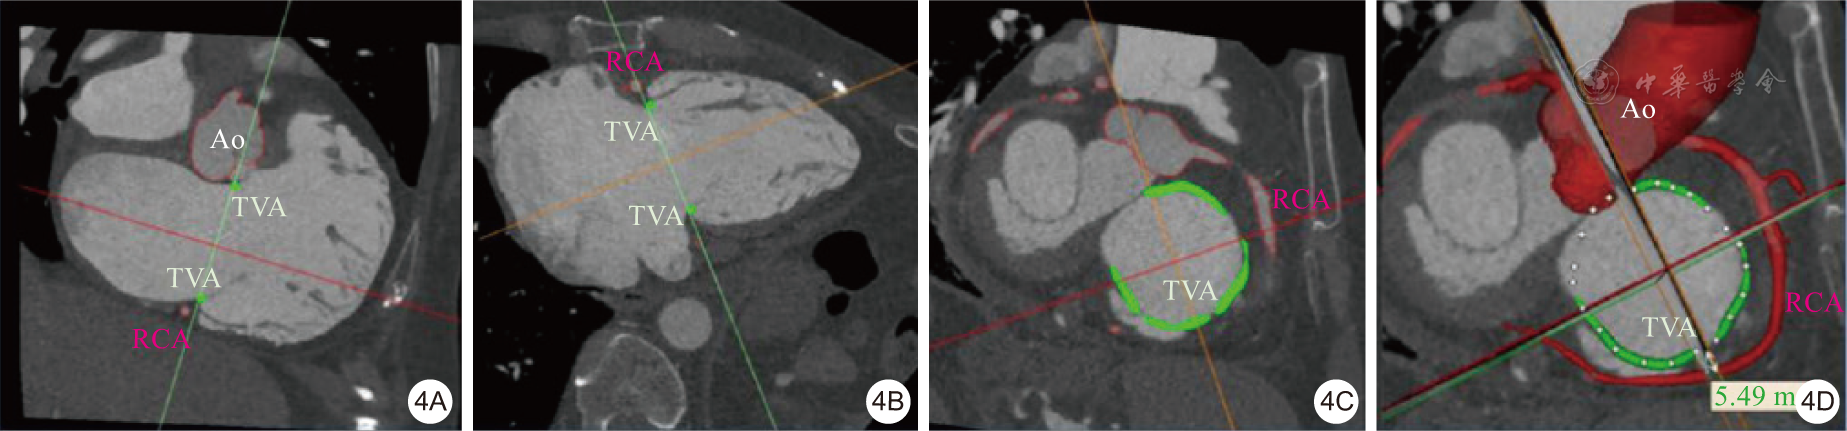

图4 三尖瓣与冠状动脉位置评估(4A为冠状面;4B为矢状面;4C为二维斜位重建;4D为三维重建)注:Ao为主动脉,TVA为三尖瓣环,RCA为右冠状动脉